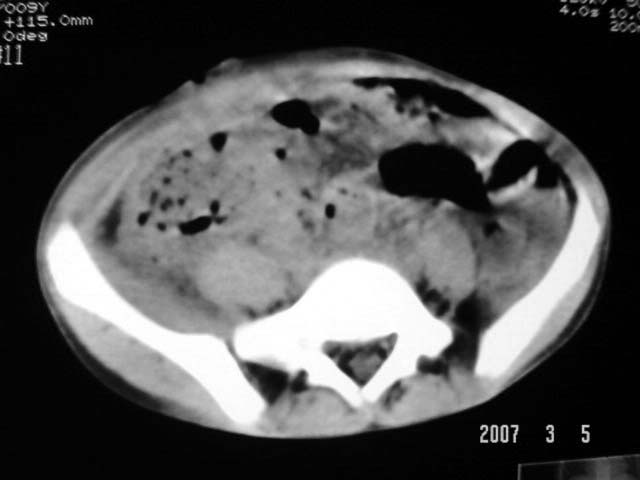

以下是引用dyqct在2007-3-5 10:28:00的发言:[br]右髂窝肿块。[br][br][br][br]